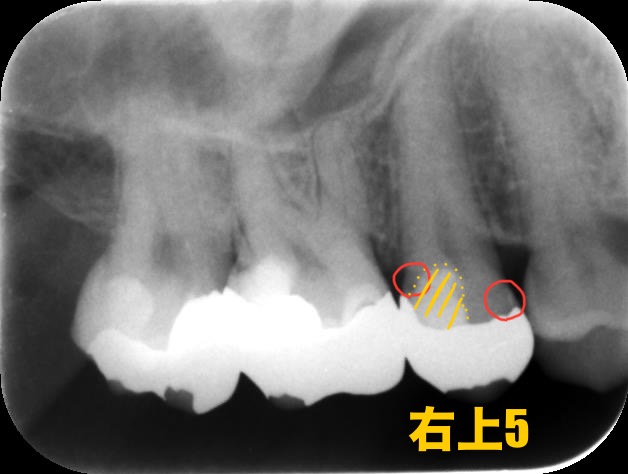

次にレントゲン写真を見てみましょう。

1回目の治療でかなり神経付近まで削ったようですね。

黄色く囲んでいるのは1回目の治療で詰められたセメントです。神経付近まで削った際に使われるもので、第二象牙質の生成を促進する効果があります。

しかしこの効果が発揮されるのは感染をきっちり取りきった時のみです。

赤く囲んだところは感染してしまっているところです。

他院では神経を抜いて被せる必要があると言われたそうですが、当院では神経を保存する処置を行っているため、まずはこの歯の神経が生きているのかどうかをEPT(電気歯髄検査)を使って確認します。